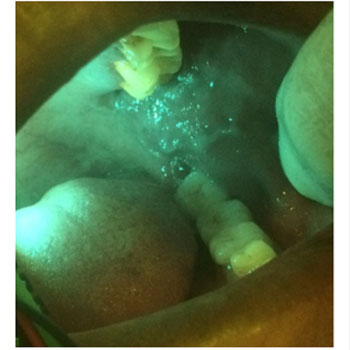

The narrow and mini head of the device can be inserted in to the oral cavity even in restricted mouth opening conditions such as OSMF and Squamous cell carcinomas to allow better visualization even in hidden areas of the oral cavity.

Lesion in Retro molar region with other oral cancer screening devices with larger head and extra oral imaging

The HD camera with 5MP will enables visualizations more clearly

Image of the lesion after filtering with smaller head and camera in the device after filtering.